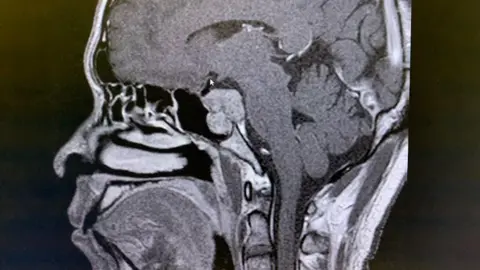

His double vision was being caused by a tumour 23mm in size at the base of his skull which was pinching a cranial nerve, but he had no other symptoms.